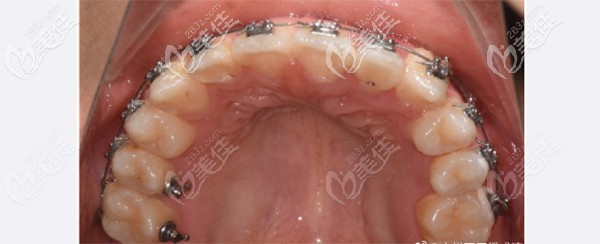

半年后我激动的拍了张上颌牙齿,真的改善蛮大的。这时候感觉找一个靠谱的医生真的太重要了。

矫正下来,在石家庄全博口腔也没花多少钱,我觉得服务和环境让我和孩子都挺喜欢的。